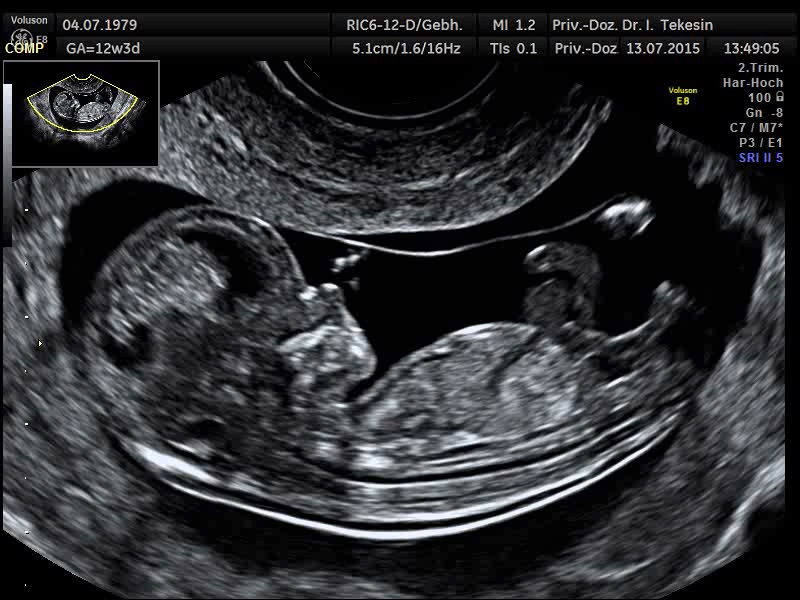

Kind in der 12. Woche

Kind in der 13. Woche